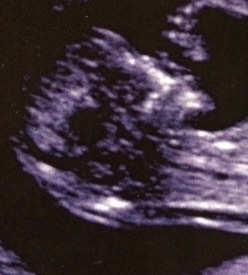

Nubs and skulls!! Please help, so many mixed reviews